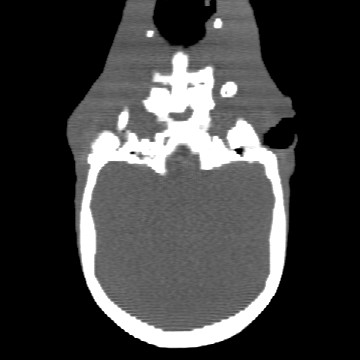

Cone-beam CT (CBCT) employs a flat-panel detector to achieve three-dimensional imaging with high spatial resolution. However, CBCT is susceptible to scatter during data acquisition, which introduces CT value bias and reduced tissue contrast in the reconstructed images, ultimately degrading diagnostic accuracy. To address this issue, we propose a deep learning-based scatter artifact correction method inspired by physical prior knowledge. Leveraging the fact that the observed point scatter probability density distribution exhibits rotational symmetry in the projection domain. The method uses Gaussian Radial Basis Functions (RBF) to model the point scatter function and embeds it into the Kolmogorov-Arnold Networks (KAN) layer, which provides efficient nonlinear mapping capabilities for learning high-dimensional scatter features. By incorporating the physical characteristics of the scattered photon distribution together with the complex function mapping capacity of KAN, the model improves its ability to accurately represent scatter. The effectiveness of the method is validated through both synthetic and real-scan experiments. Experimental results show that the model can effectively correct the scatter artifacts in the reconstructed images and is superior to the current methods in terms of quantitative metrics.